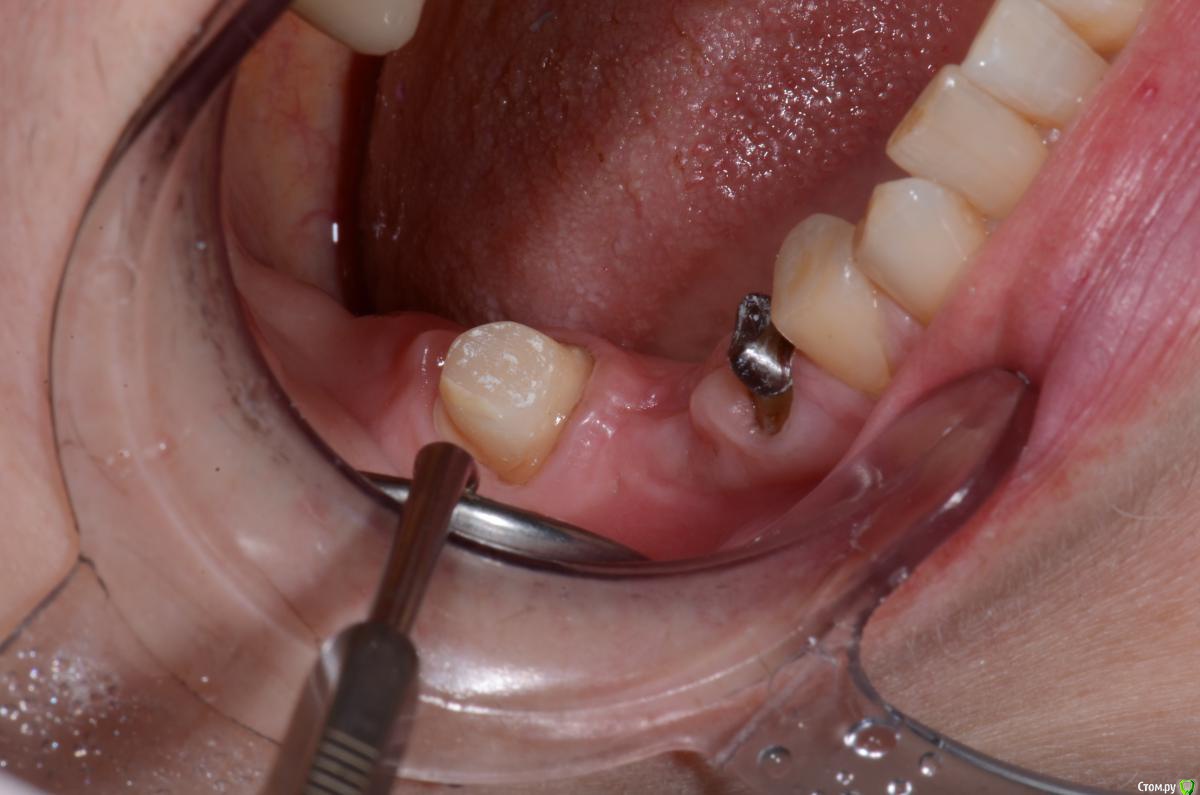

DimaKoleso Опубликовано 23 января, 2016 Поделиться Опубликовано 23 января, 2016 Решил выбросить на всеобщее обозрение вот такую работу. Ваше мнение? Делаете ли Вы гирлянду? В данном случае 47 зуб гирлянда 360, 45 зуб гирлянда 180 6 Ссылка на комментарий

MaxDok Опубликовано 24 января, 2016 Поделиться Опубликовано 24 января, 2016 Вкладка в 45 Ваша ? Ссылка на комментарий

Romanson Опубликовано 24 января, 2016 Поделиться Опубликовано 24 января, 2016 А снимок есть? Ссылка на комментарий

DimaKoleso Опубликовано 25 января, 2016 Автор Поделиться Опубликовано 25 января, 2016 Вкладка в 45 Ваша ? вкладку терапевт устанавливала, у них в клинике, когда я пришел, терапевты сами вкладки делали Ссылка на комментарий

DimaKoleso Опубликовано 25 января, 2016 Автор Поделиться Опубликовано 25 января, 2016 А снимок есть?снимок есть, качество плохое Ссылка на комментарий